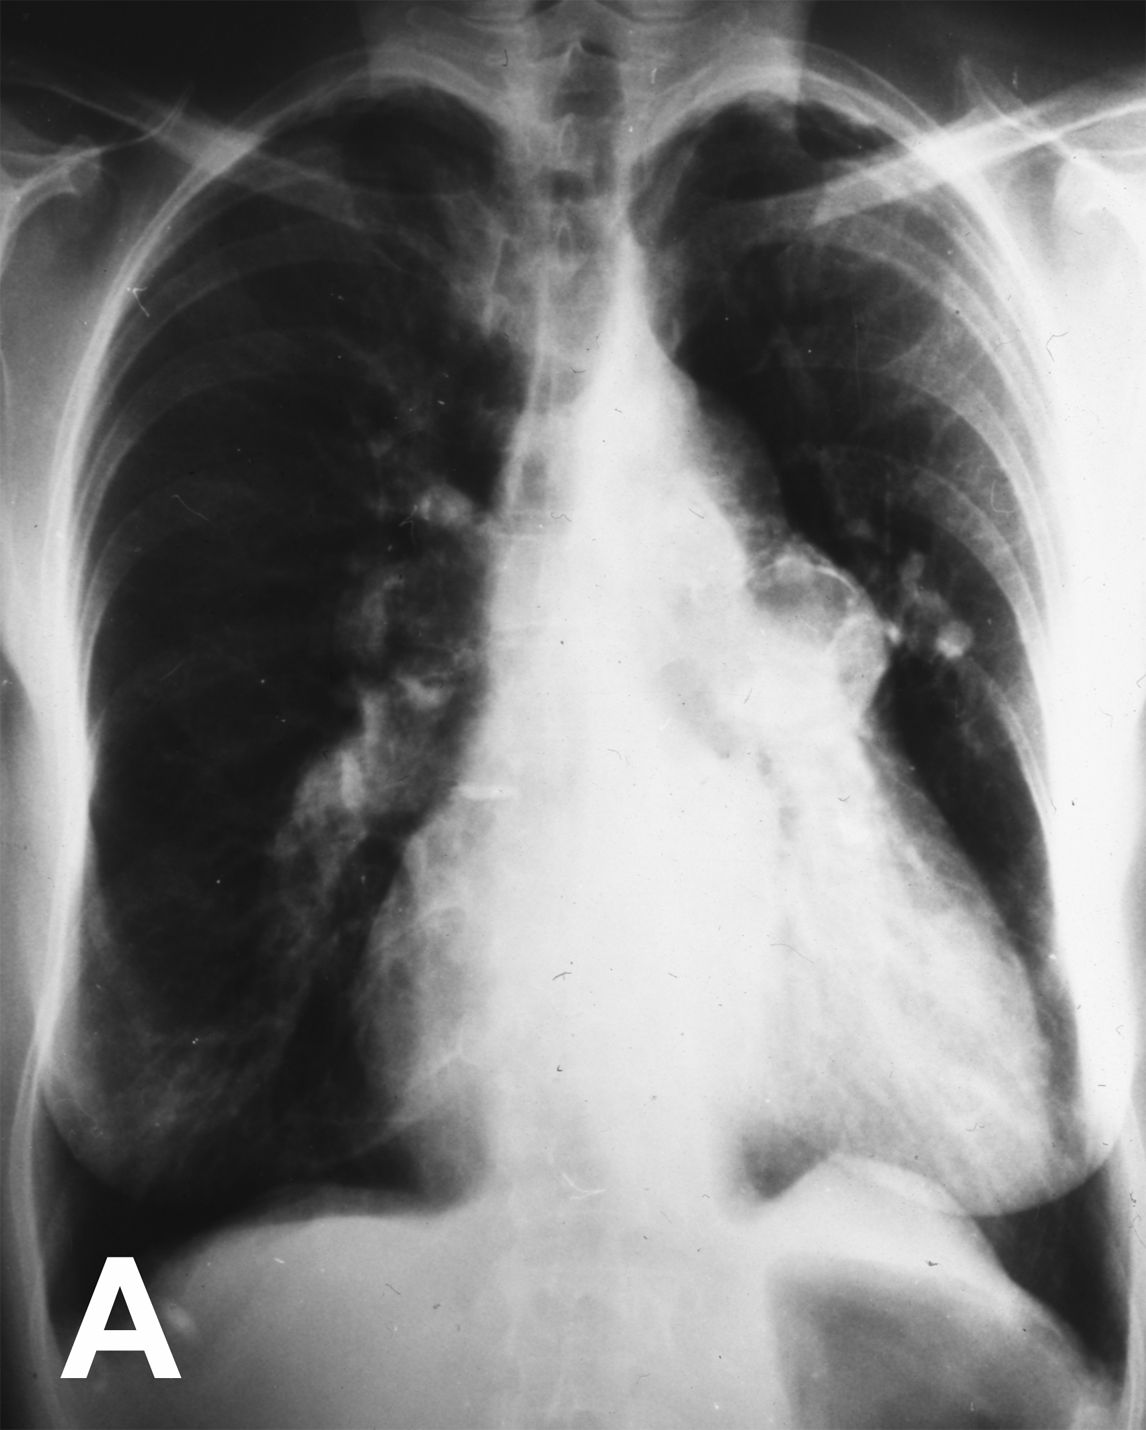

Chest X-ray showed significantly dilated pulmonary vessels and a round calcified mass in the left pulmonary hilum (Figures 1A, 1B). The patient died suddenly on the following day. Autopsy revealed a large (28 mm) communication between the pulmonary trunk and the aorta (Figure 2).

Figure 1: A) Chest radiograph demonstrating dilated pulmonary vessels and, B) round calcified mass in the left pulmonary hilum.